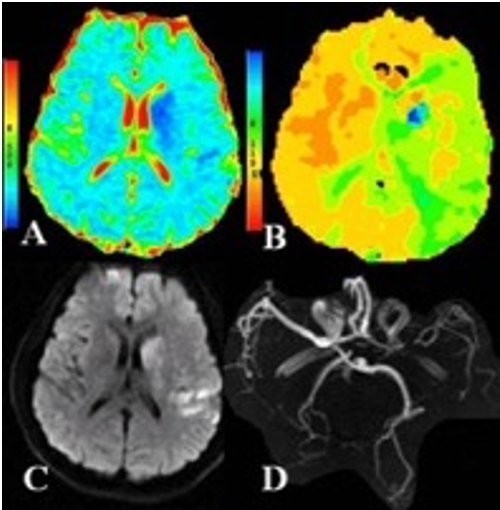

Les traitements de reperfusion à la phase aiguëont vu leurs indications considérablement élargisavec de nouvelles moda lités thérapeutiques[1] . La thrombolyse intraveineuse par alteplase a montré son efficacité jusqu' à 9h suivant l'installation des symptômes et pour les accidents ischémiques cérébraux du réveil ou d'horaire inconnue pour certains patients. Ces patients candidats à une thrombolyse intraveineuse au-delà de 4h30 sont identifiables grâce à une imagerie avancée (scanner ou IRM avec séquences de perfusion, voir figure) montrant un mismatch (différentiel entre le core ischémique et la zone hypoperfusée viable ou pénombre ischémique). Un autre thrombolytique, la tenecteplase, forme génétiquement modifiée d'alteplase, apparaît comme une alternative plus simple d'utilisation et possiblement plus efficace que l'alteplase. En cas d'accident ischémi que cérébral avec occlusion d'une artère cérébrale proximale, la thrombectomie mécanique (TM) améliore significativement le pronostic fonctio nnel pour les patients traités dans les 6 heures après le début des symptômes. La TM peut également être efficace jusqu'à 24h après les premiers symptômes chez certains patients avec mismatch. La TM apparait au vu des derniers essais également une option thérapeutique efficace pour améliorer la récupération des patients avec accident ischémique cérébral sévère étendu. La fenêtre thérapeutique des traitements de reperfusion s'est élar gie dans l'accident isché mique cérébral, mais le concept «time is brain» reste toujours aussi pertinent avec la nécessité d'organiser des filières de soins autour de l'alerte AVC. Un moyen prometteur pour administrer le traitement le plus rapidement possible repose sur des unités vasculaires mobiles (MSU «mobile stroke unit») avec un scanner embarqué dans le camion médicalisé des premiers secours permettant la réalisation immédiate de l'imagerie et l'administration de la thrombolyse intraveineuse dans le camion. Plusieurs essais comparatifs ont démontré le bénéfice des MSU pour améliorer les délais et, critère essentiel, le devenir fonctionnel des patients.

Figure Imagerie cérébrale multimodale en Scanner de perfusion et IRM d'un accident ischémique encours de constitution réalisé à 7 h des débuts des symptômes. Le coeur (ou core) de l'infarctus cérébral est visible en A (en bleu foncé) et C (Diffusion). Il existe une vaste zone hypoperfusée (C) dans le territoire de l'artère sylvienne G témoignant d'une zone de pénombre ischémique avec un tissu potentiellement viable. L'ARM du polygone de Willis (D) montre une interruption sur le premier segment de l'artère sylvienne gauche en rapport avec un thrombus.